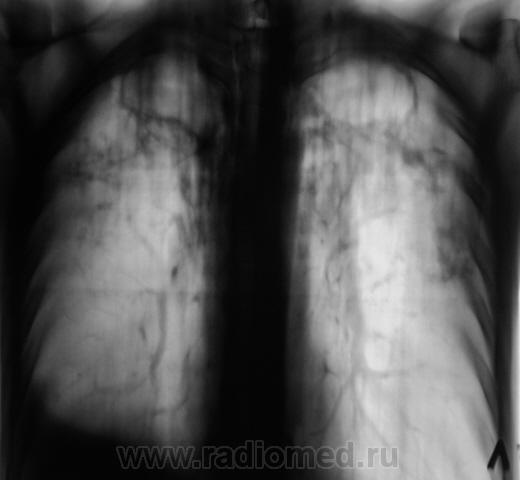

Мужчина, работает в областном центре, "в охране". Приехал проведать маму, так как мама заболела. На 3 день почувствовал себя "не очень" и решил обратиться в местную поликлинику к терапевту. В регистратуре выяснили, что мужчина в течение 3-х лет профилактическую флюорографию не проходил и направили во флюорографический кабинет.

Сразу-же, после производства флюорограммы, пациент был дообследован в рентгенодиагностическом кабинете согласно стандарту.

добрый день. мама как раз может и не болеть.а у ее сына хороший инфильтративный туб-з с распадом и обсеменением,но процесс не "свежий",есть объемное уменьшение в\д справа,нет перикавитарной инфильтрации,но активный. из вновь приобретенной патологии-экссуд.плеврит справа. немного удивляет:б-ой из области,скорее всего "обязательный контингент" ,и рфо более 3лет.иногда из иту приходят с меньшими процессами. в мокроте нашли куб?

1. Я выставил без "всяких" фиброзно-кавернозный. Далее коллеги-фтизиатры разберутся.

Фтизиатры согласились с ФКТ, палки при микроскопии - море.